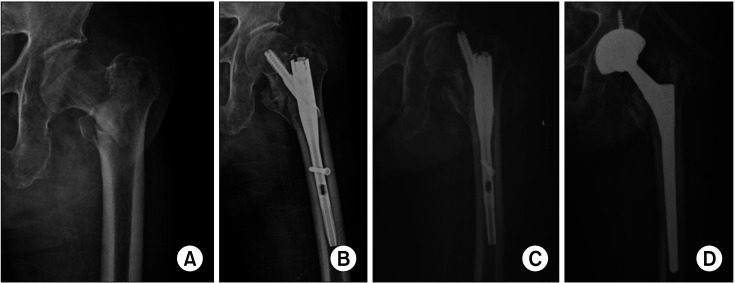

Backgroud: Conversion to total hip arthroplasty (THA) is the most common treatment for older patients following failed hip fracture fixation. However, the dislocation rate after conversion THA is higher than that after primary THA for arthritis. Recent studies have reported that a dual-mobility (DM) cup has a lower dislocation rate than fixed-bearing (FB) THA. This study aimed to assess the outcomes of conversion THA using a DM cup for failed hip fracture fixation.

Methods: Between April 2015 and June 2021, 116 patients underwent conversion THA for failed hip fracture fixation at a tertiary hospital. Among them, 83 and 33 cases using the FB and DM cups, respectively, were included in the study. The following outcomes were assessed and compared between the 2 groups: reoperation, dislocation, intraprosthetic dissociation (IPD), periprosthetic fracture, deep joint infection, and modified Harris hip score (mHHS).

Results: There were no significant differences between the FB and DM groups in terms of radiological outcomes, reoperation, IPD, periprosthetic fracture, deep joint infection, or mHHS. In particular, there was no statistically significant difference in the dislocation rate between the FB and DM groups (6.02% and 3.03%, respectively; p = 0.673).

Conclusions: The dislocation rate in the DM group was lower than that in the FB group, with a relative risk of 0.50, although this difference did not reach statistical significance. These findings suggest that DM implants may be potentially beneficial options in such cases; however, further research is required to confirm this trend.